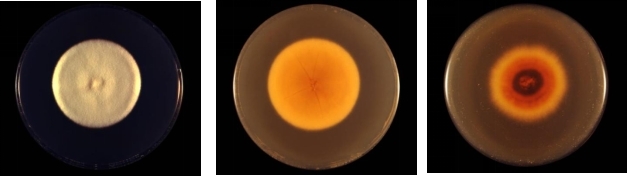

在实验室培养条件下,须癣毛癣菌在沙氏培养基上培养1-2周后,会形成具有特征性的菌落。有研究报道,从病兔身上分离的须癣毛癣菌菌落形态为白色粉末状,质地细腻,表面可能呈绒毛状或粉末状。